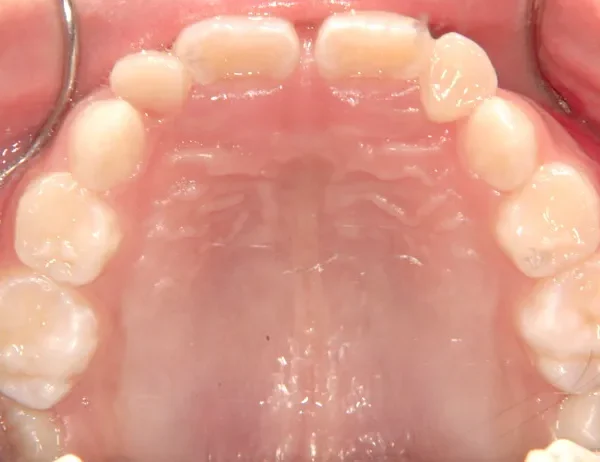

【子供の矯正(一期)】叢生・開咬・前歯で噛めない・舌癖・7歳女児【M.O様】

治療終了後

治療回数31回、4年11ヶ月の治療期間で矯正治療を終了しました。

主訴が改善され、ご満足頂きました。